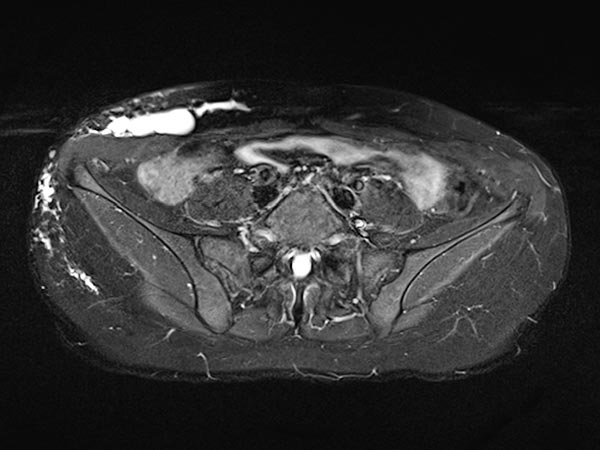

Die transversale, T1-gewichtete, fettunterdrückte MRT nach Kontrastmittelgabe zeigt nur ein minimales Enhancement der dünnen Wände der lymphatischen Malformation. Dies ist typisch für eine LM.